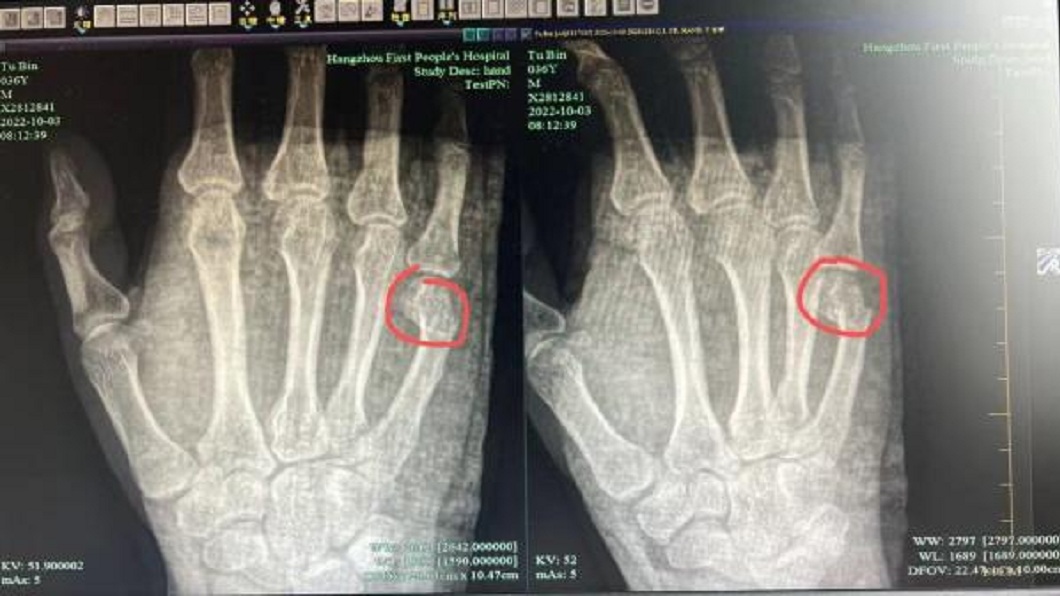

▼吳男本以為自己用力過猛,過一下子就好了,但隔天右手掌出現紅腫,疼痛非但不見好轉,反而變得更加嚴重。他連忙去醫院檢查,經過X光照顯示,吳男右手第5掌骨骨折,斷裂部分明顯移位,必須住院治療。對此,吳男無奈說:「有時真的是忍不住,還好這一拳是打在桌子上,要是打在孩子身上,麻煩就大了。」

杭州市第一人民醫院骨科副主任范小良則提醒說:「別以為拳頭很硬,其實第五掌骨很脆弱。」范小良表示,第五掌骨骨折是常見的手部骨折,大多數出現在握拳狀態下直接創傷所致,又稱「拳擊手骨折」。因為吳男骨折的位置經常活動,所以不容易痊癒,存在骨折移位和畸形癒合的風險,如果之後出現不適情況,一定要及時到骨科門診回診。